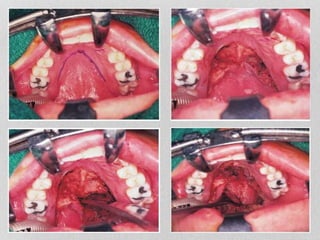

• Medial maxillectomy approach:

For tumors extending to pterygopalatine fossa

Soft tissue elevation preferably with a midfacial degloving

incision. Advantages are:

Excellent exposure of lesion

Direct control of internal maxillary artery in pterygopalatine

fossa

Very satisfactory cosmetic outcome

• Commonest complication – Vestibular stenosis, Infraorbital

N. Injury

lateral rhinotomy only required when superior parts of

• Medial maxillectomyapproach: For tumors extending to pterygopalatine fossa Soft tissue elevation preferably with a midfacial degloving incision. Advantages are: Excellent exposure of lesion Direct control of internal maxillary artery in pterygopalatine fossa Very satisfactory cosmetic outcome • Commonest complication – Vestibular stenosis, Infraorbital N. Injury lateral rhinotomy only required when superior parts of ethmoids are to be dissected